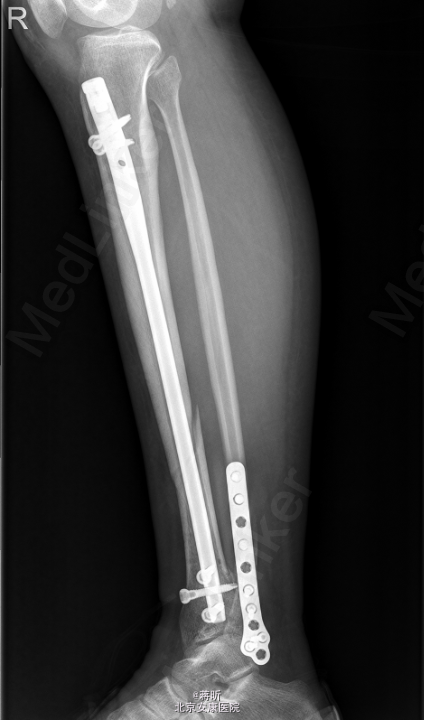

患者,女,32岁,因“右侧胫腓骨骨折术后1月余,发现下肢窦道1周”入院。 患者1月余前因外伤致右侧胫腓骨骨折,于2015-03-24在我院行“右胫骨骨折闭合复位内固定术+右腓骨骨折切复内固术”,术程顺利,术后恢复可,常规拍片复查,1周前自检发现右下肢膝关节处及外踝处出现窦道,伴流脓,无下肢麻木,无感觉异常,无发热寒战等其他不适,患者遂来我院就诊,门诊拟“骨折术后感染收住入院”。既往有“1型糖尿病”病史8年。

右小腿皮温稍高,右膝关节及踝关节活动未受限,右膝及右外踝处可见2处手术疤痕,分别长约7cm及5cm,愈合尚可,右膝正中及右外踝可见3处窦道,可见脓液流出,右足背动脉搏动可及,末梢各趾血循、感觉、活动正常。余肢体无殊。 2015-4-27我院拍片示:右胫骨中下段骨折术后复查。

初步诊断: 1,右胫腓骨骨折术后感染;2,1型糖尿病 处理:[右侧]胫腓骨骨折术后感染清创VSD+右踝内固定拆除术